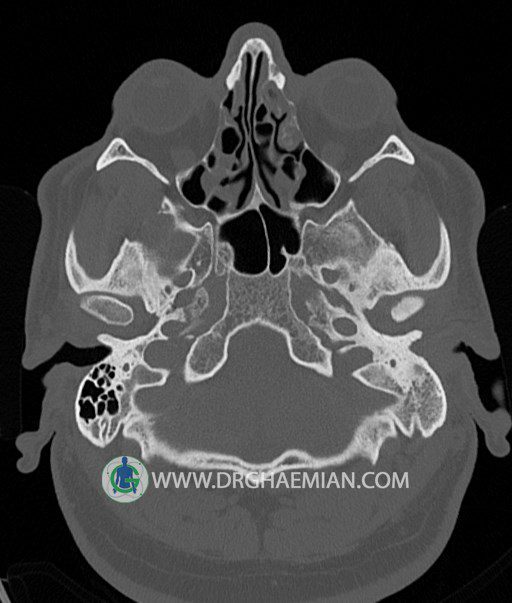

سی تی اسکن گوش داخلی به رادیولوژیست اجازه می دهد تا سطوح مختلف، یا اسلایس هایی از استخوان های که از جمجه به گوش می روند را از طریق امواج ایکس چرخشی مشاهده کند. در این کیس اودیت مدیا، ماستوئیدیت مزمن، اوتیت خارجی، انحراف سپتوم بینی، کونکا بولوزا و افزایش ضخامت سینوس ها مشاهده می شود.

در HRCT از استخوان تمپورال با مقاطع آگزيال ، ساژيتال و کرونال ظريف ( 0.6 mm ) :

– نماي کوکلهآي دو طرف با 2.5 دور گردش مجرا

– نماي cochlear aqueduct

– نماي semicircular canal خلفي ، لترال ، فوقاني و وستيبول

– استخوانچه هاي گوش داخلي شامل malleus ، incus و stapes (دنسيتي و رديف استخوانچه ها )

– نماي oval window و round window ، tympanic cavity ، attic و کانال گوش داخلي

– کانال عصب فاشيال و مسير ان از ناحيه کانال گوش داخلي ، geniculate ganglion تا محل خروج ان از stylomastoid foramen

– نماي tympanic membrane ، کانال ICA ، بولب جوگولار دو طرف

در حد طبيعي است .

– اپاسيتي گوش مياني چپ ناشي از وجود دانسيته نسج نرمي دراطراف استخوانچه ها همراه با اروژن اسکوتوم و

استخوانچه ها بدون جابجايي در رديف استخوانچه ها مشهود است که مطرح کننده اوتيت مديا همراه با نشانه

هاي مشکوک به کولستئاتوم مي باشد .

– اپاسيتي و اسکلروزيس ماستوئيد چپ نشانه ماستوئيديت مزمن

– اپاسيتي کانال گوش خارجي ناشي از دانسيتي نسج نرمي مطرح کننده external otitis

– انحراف سپتوم مياني بيني به راست

– کونکا بولوزا در کونکاي مياني چپ و

– افزايش ضخامت مخاطي در سينوس هاي اتموئيد و ماگزيلاري

اپاسيته